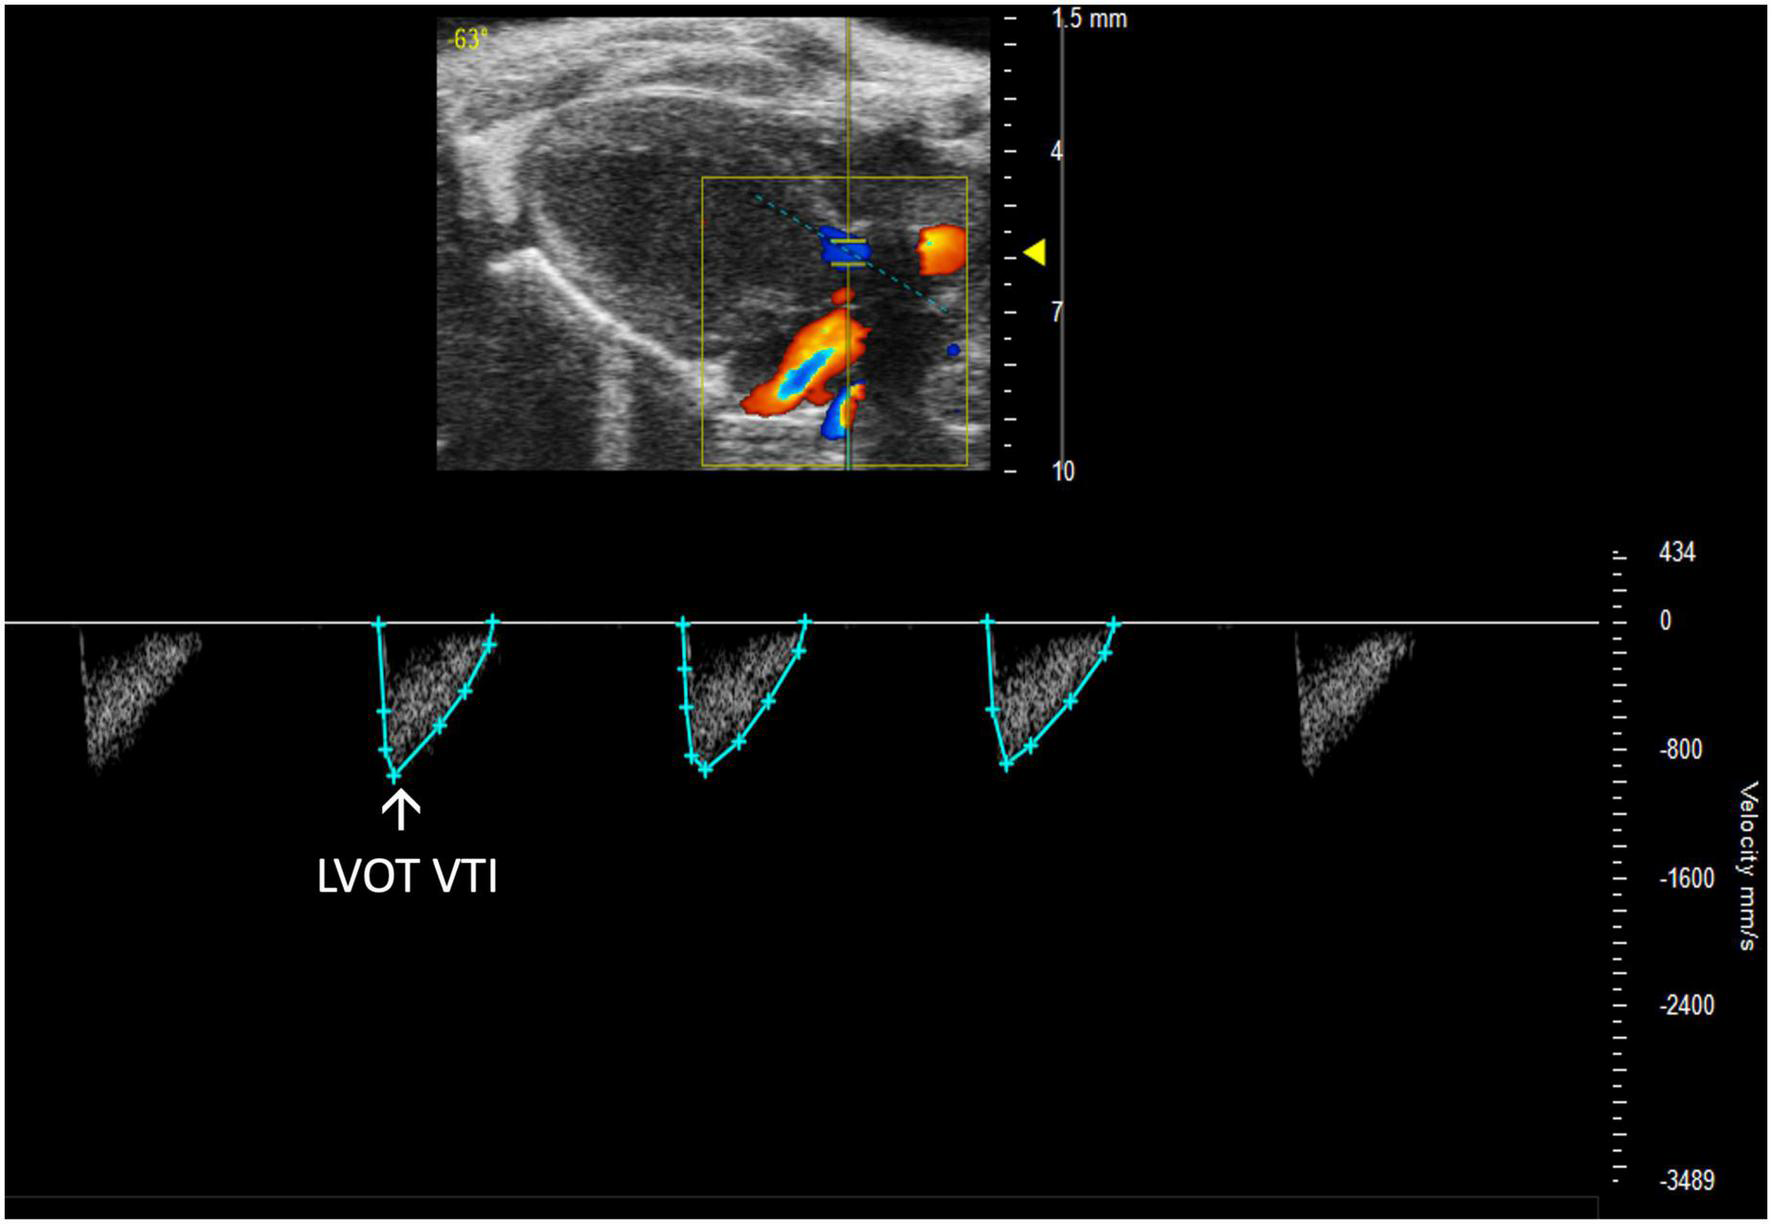

2.3.2.2 Left ventricular outflow tract velocity time integral

Left ventricular outflow tract velocity time integral (LVOT VTI) is defined as a measurement of blood flow out of the ascending aorta. It can be measured as the area under the curve in a PLAX PW Doppler mode image with the cursor over the flow of the ascending aorta (Figure 10). LVOT VTI has been shown to be representative of CO in humans and more predictive than EF or Doppler derived CO in patients with heart failure (10). Thus, we hypothesize that LVOT VTI is an accurate measure of systolic function and CO in mice as well, but this remains an interesting area of study for future directions. LVOT and LVOT VTI can be used to calculate SV, CO, and AVA:

FIGURE 10

Representative image displaying left ventricular outflow tract velocity time integral (LVOT VTI), a measure of blood flow out of the ascending aorta which is obtained by calculating the area under the curve in the PW Doppler mode of the parasternal long axis view.